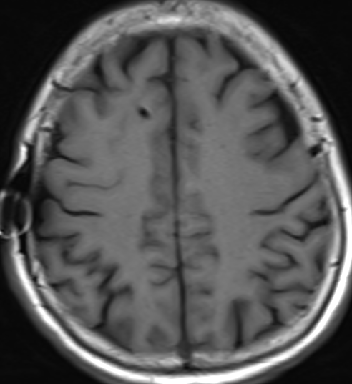

2014-10-17 CT

仍时有前额部疼痛,程度轻,调压190—200